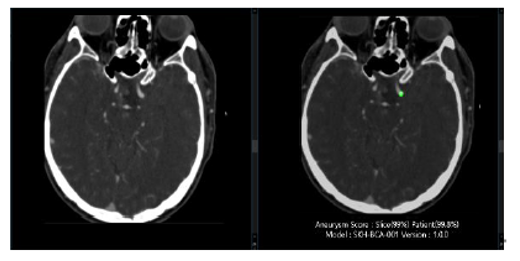

Detects and localizes unruptured cerebral aneurysms using deep learning. Marks aneurysm locations, outlines, and diameter ranges on CTA images.